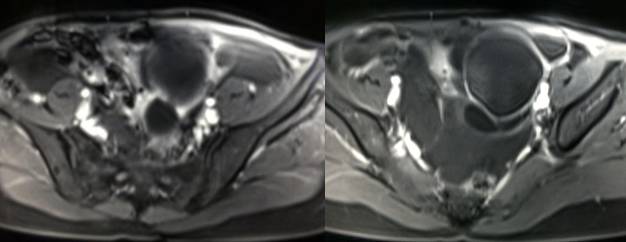

MR检查:

病理结果:黄体血肿

黄体血肿为正常排卵过程中,卵泡层破裂,引起出血,较多的血液潴留在卵泡或黄体腔内形成血肿。

正常黄体直径为15mm左右,以后转折为白体,并在下一个周期的卵泡期自然消退。若黄体内出血量较多,则形成黄体血肿,或称黄体内出血,出血性黄体。黄体血肿多为单侧,一般直径为40mm,偶可达100mm,黄体血肿被吸收后可导致黄体囊肿,较大的血肿破裂时可出现腹腔内出血,剧烈腹痛、少量阴道流血和腹膜刺激征,不易与宫外孕区别。

根据时间不同MR信号也有所不同,TIWI脂肪抑制序列可以鉴别脂肪和出血。